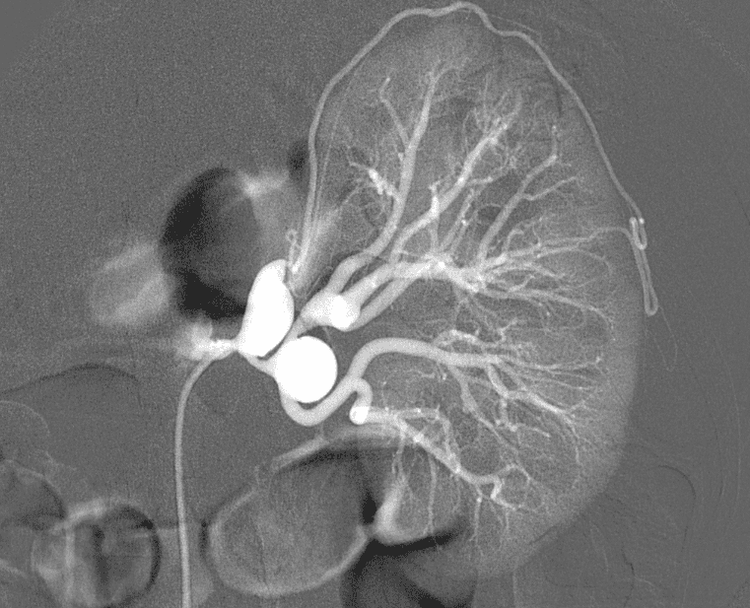

Hình ảnh chụp mạch bệnh nhân bị phình động mạch thận

Phình động mạch thận là tình trạng thành động mạch thận bị giãn không hồi phục với đường kính lớn hơn 50% so với đường kính bình thường. Có nhiều nguyên nhân gây phình động mạch như:

Phình động mạch thận cũng như phình động mạch nói chung nếu không được điều trị thì luôn có xu hướng to lên và có thể dẫn tới các biến chứng như: chèn ép các cơ quan xung quanh, nhiễm khuẩn, vỡ túi phình,... Đối với phình động mạch thận, vỡ túi phình vào ổ bụng hay sau khoang phúc mạc là tai biến nguy hiểm nhất, bệnh nhân sẽ bị chảy máu ồ ạt, nguy cơ tử vong cao. Dù có được phẫu thuật kịp thời thì tỷ lệ tử vong vẫn lên đến 30-70%.

Bệnh nhân phình động mạch thận cần được theo dõi chặt chẽ, khi kích thước túi phình động mạch to lên thì phải được theo dõi sát hơn. Phình động mạch thận sẽ được chỉ định mổ khi:

• Đường kính túi phồng ≥ 5 cm hoặc đường kính tăng hơn 0.5 cm/năm

• Phình động mạch thận có biểu hiện lâm sàng

• Phình động mạch hình túi vì có nguy cơ cao gây bội nhiễm và vỡ đột ngột.